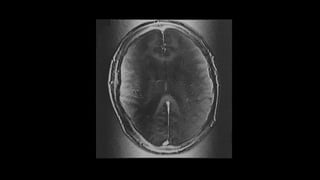

El artefacto de movimiento codificado en fase es uno de los

Se manifiesta como efecto fantasma en la dirección de la codificación de

fase, generalmente en la dirección del eje corto de la imagen (es decir, de

izquierda a derecha en los cerebros axial o coronal, y anterior a posterior

en el abdomen axial).

Estos artefactos se pueden ver en las pulsaciones arteriales, la deglución,

la respiración, el peristaltismo y el movimiento físico de un paciente.

Cuando se proyecta sobre la anatomía, puede simular una patología y

necesita ser reconocida. El movimiento aleatorio, como el movimiento del

paciente, produce un borrón en la dirección de la fase. El movimiento

periódico, como la pulsación respiratoria o cardíaca / vascular, produce

fantasmas discretos y bien definidos. El espacio entre estos fantasmas

está relacionado con el tiempo de repetición (TR) y la frecuencia del

movimiento.